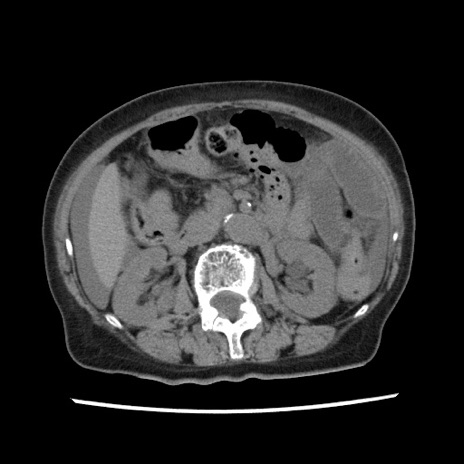

症例1(横断像)

【症例】80歳代女性

【主訴】腹痛

【現病歴】8時間前から腹痛あり来院。

【既往歴】糖尿病、脂質異常症、子宮体癌にて子宮全摘術

【身体所見】意識清明・会話良好だが腹痛で苦悶様、全腹部にわたって反跳痛と圧痛あり

【データ】WBC 13600、CRP 0.14、LDH 224、CK 90